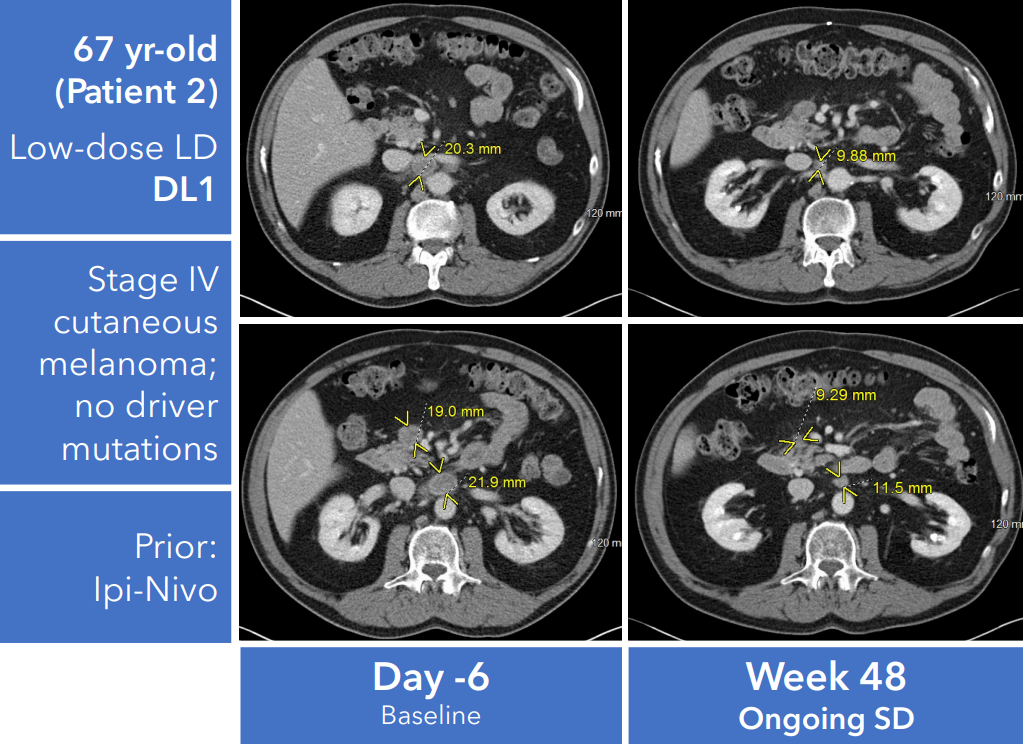

随着技术水平不断提升,人们对癌症的探索逐渐深入,癌症治疗的策略也在不断改变。而近年来,利用免疫系统来对抗癌细胞被发现是一种非常具有潜力的治疗方式。其中肿瘤浸润淋巴细胞(TIL)疗法已成为一种有前途的实体瘤治疗策略,并在2024年被批准用于既往接受过免疫检查点抑制剂和BRAF/MEK靶向治疗(如适用)的晚期黑色素瘤患者。